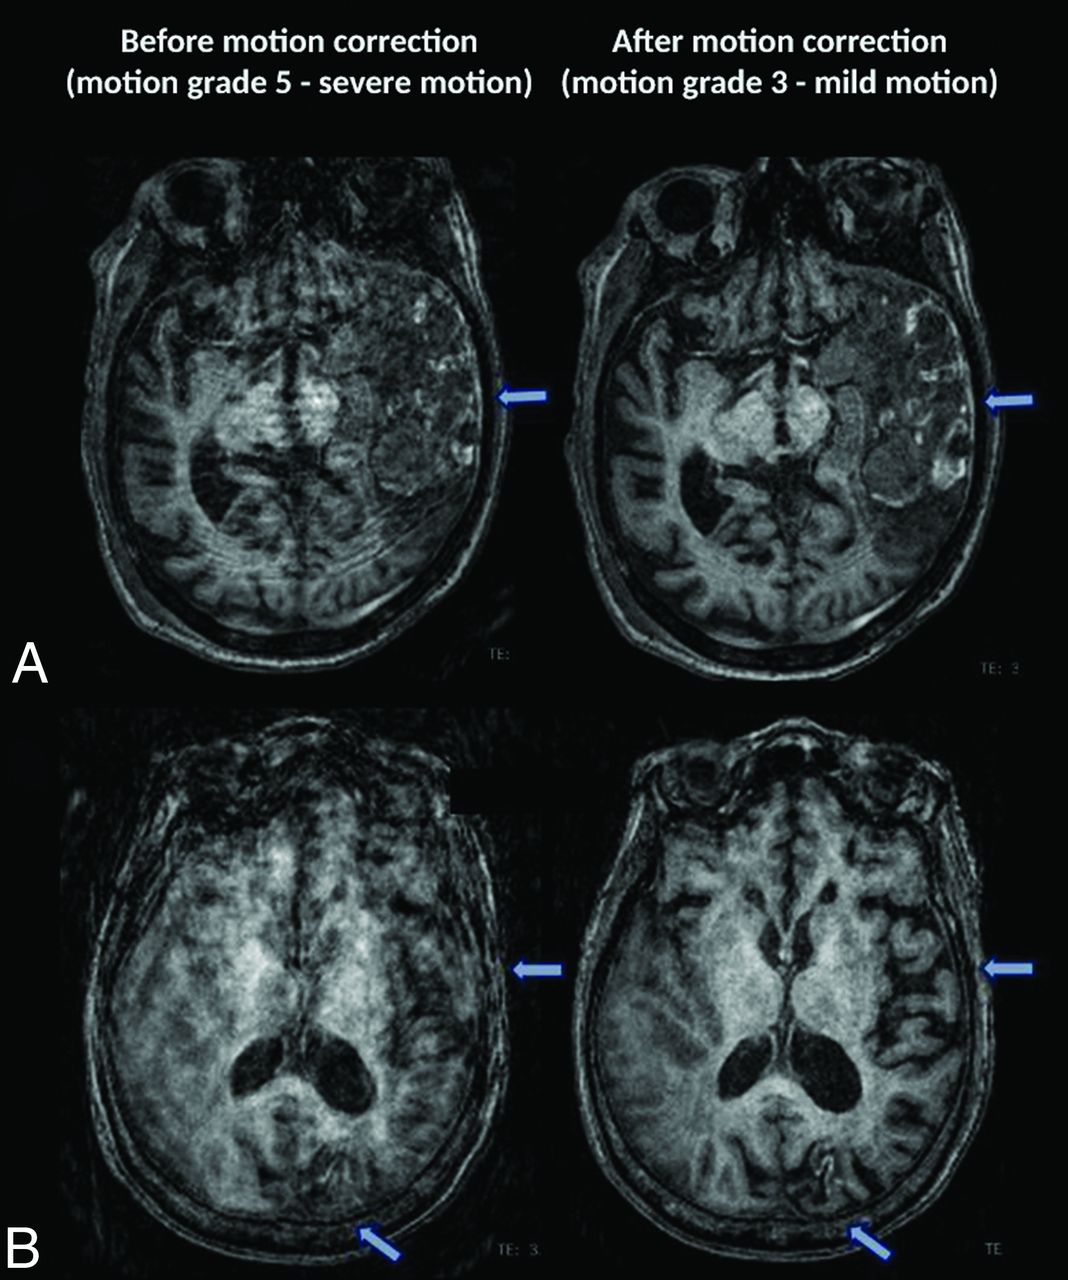

Two neuroradiologists (M.L. and J.F. with 3 and 5 years of experience, respectively) performed independent blinded reviews of unlabeled MPRAGE images without and with SAMER motion correction. The order of the study and the type of study (baseline-versus-SAMER motion-corrected images) were randomized by A.T. for the reviewing neuroradiologists. Cases with any discrepant grades were adjudicated independently by a third blinded senior neuroradiologist (J.C.) with >10 years of experience. A previously established 5-point motion scale was used for grading (Fig 1).1 Grade 1 indicates the absence of detectable motion artifacts; grade 2 indicates minimal motion with barely detectable motion artifacts and a negligible effect on image quality and diagnosis; grade 3 indicates mild motion with noticeable motion artifacts that likely do not have diagnostic consequences; grade 4 indicates moderate motion artifacts that degrade and possibly obscure underlying pathology; and grade 5 indicates severe motion artifacts that distort anatomy and obscure underlying pathology. Grades 1, 2, and 3 were considered diagnostic quality with regard to motion artifacts, whereas grades 4 and 5 were considered nondiagnostic, as defined in the original article by Andre et al.1 The motion grade improvement was defined as the precorrection motion grade minus the postcorrection grade.

Motion scale used for the clinical quantification of motion artifacts along with representative cases before motion correction. The arrows point to areas of image blurring due to motion artifacta.